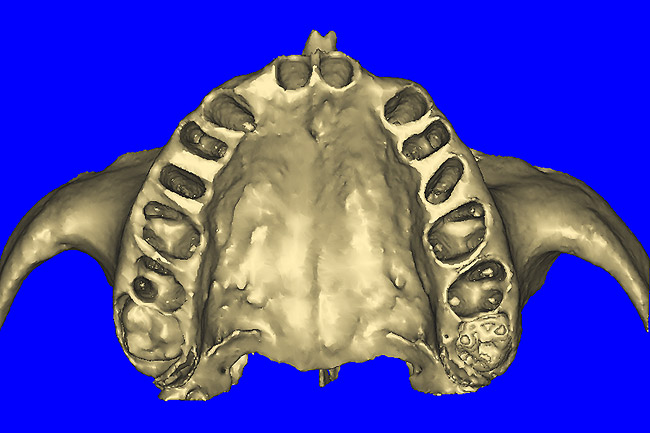

After the basic plan had been established, it was re-evaluated using interactive 3D images. The reconstructed 3D view of the maxilla clearly illustrated the extent of the bilateral facial concavities, and the root eminences of the adjacent and posterior teeth (Figure 7A). The placement of the virtual implants then was evaluated to ensure that the facial cortical plate was not perforated (Figure 7B). The implants were labeled individually as “7” and “10,” with the simulated yellow abutment projection indicating the facial-lingual inclination through the bone to the level above the incisal edge of adjacent teeth. The ability to gain a better understanding of these individual root forms can not be underestimated. The dental literature has suggested certain parameters for placing implants near teeth and implants next to other implants. However, there is little scientific 3D documentation to support these suggested rules.5-10 The use of an interactive treatment-planning software application permits closer scrutiny of previously difficult-to-visualize areas, and can now be used to redefine perceptions of spatial positioning of implants, especially when in close proximity to natural tooth roots, vital anatomy, and adjacent implants.27-29

Using different masking (segmentation) and threshold Hounsfield unit values, several new 3D bone volumes can be created which offer invaluable information. To help determine the final position of each implant a new bone model was created with a Hounsfield unit value of 1480, which eliminated all but the densest objects included in the scan data. (Results may vary depending on the CBCT machine used.) The inner and outer layers of bone were removed, leaving the underlying enamel and root structure of the teeth (Figure 8A). After the bone had been stripped away, the root inclinations were examined closely. The most striking findings confirmed the rotated position of the right central, while revealing the slight mesial dilaceration of the root apex, which converged on the space needed for the path of the potential implant (Figure 8B). The schematic shapes of the proposed implants were visualized for the right and left lateral spaces in different rotations of the 3D maxillary arch. It was at this point that a determination was made as to the appropriate implant shape and type that would fit the available space while avoiding encroachment on adjacent tooth roots. A tapered design implant (Tapered Screw-Vent®, Zimmer Dental, www.zimmerdental.com) was chosen from the large virtual library. With the SIMPlant software, the virtual library contains data from dozens of implant manufacturers and realistic.computer-aided design representations as seen in Figure 9A through the translucent bone. The position of the left implant can be visualized with adequate mesial-distal distance between adjacent tooth roots (Figure 9B) and a more delicate placement (Figure 9C).

Figure 8a  By using the masking feature, the inner and outer layers of bone were removed virtually, revealing (A) the enamel and root structure of the teeth and the rotated position of the right central and (B) a slight mesial dilacerations of the root apex.

Figure 8a

Figure 8b  By using the masking feature, the inner and outer layers of bone were removed virtually, revealing (A) the enamel and root structure of the teeth and the rotated position of the right central and (B) a slight mesial dilacerations of the root apex.

Figure 8b